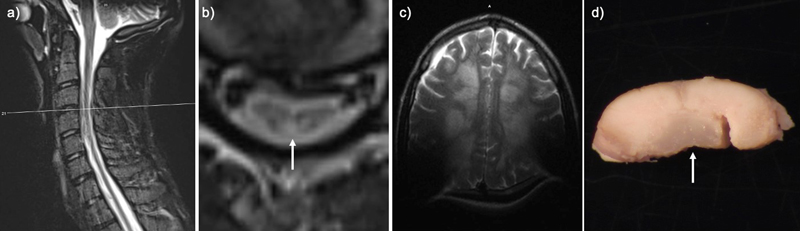

An 11-year-old boy presented with ocular keratopathy, clumsiness, sensory ataxia, bilateral hearing loss, and hyporeflexia. He developed progressive myeloneuropathy; imaging showed a longitudinally extensive lesion preferentially involving the dorsal columns (Fig. 1a–b). The patient was extensively investigated, and other known causes of longitudinally extensive transverse myelopathy were ruled out, including neoplastic/paraneoplastic, infectious, mitochondrial and other known metabolic disorders, neurodegenerative, toxic exposures, and autoimmune conditions. For additional details on clinical course please see paper Chung et al., 2020 supplemental document Methods S1 [1]. Initially, the brain was relatively unaffected on imaging. The spinal cord disease progressed to involve the anterolateral cord. At age 13 a peripheral nerve biopsy showed mildly abnormal myelin profiles and ongoing and chronic axon loss [1]. An Undiagnosed Diseases Network evaluation uncovered a novel de novo heterozygous ACOX1 N237S variant. He suffered a relapsing and remitting course with overall progressive decline despite treatment with N-acetyl cysteine, plasmapheresis, intravenous immunoglobulin, corticosteroids, rituximab, cyclophosphamide, and tocilizumab [1]. At 19, he was admitted for a urinary tract infection and developed encephalopathy and neuromuscular respiratory failure requiring mechanical ventilation. Brain MRI showed new, diffuse, bilateral subcortical Fluid-Attenuated Inversion Recovery (FLAIR) and T2-weighted Turbo Spin Echo (TSE) hyperintensities with U-fiber sparing, consistent with disease progression (Fig. 1c). The patient passed away after elective extubation and underwent a complete autopsy within 24 hours after death. To date, an additional 30 cases have been identified.

Figure 1: Perimortem imaging and gross pathology

T2-weighted Turbo Spin Echo (TSE) sequence in the transverse (TRA) plane of a) sagittal cervical cord, b) transverse cervical cord showing hyperintensity of the dorsal column (arrow), and c) axial brain with artifact due to cochlear implants. d) Post fixation cross-section of the cervical cord with translucency of the dorsal column (arrow).

Grossly, the spinal cord showed translucency and discoloration of the dorsal column throughout, but particularly in the cervical cord (Fig. 1d). Microscopically there was total destruction of the dorsal columns with loss of myelin, loss of axons, and reactive gliosis (Fig. 2a–b, d–e, g–h, j–k). Areas near the dorsal column showed relative preservation of the axonal array with gliosis (Fig. 2c, f, i, l) and active macrophage infiltrate showed with a CD68 stain (Fig. 3a). In addition, there was pallor and vacuolation in the anterior and lateral corticospinal tracts. CD68 immunostain highlighted macrophages most prominent in the corticospinal tract in a perivascular distribution with PAS-positive intracytoplasmic material corresponding to digested myelin. There were few scattered oligodendrocyte transcription factor 2 (Olig2) positive oligodendrocytes. The cervical and thoracic cord showed neuron loss and atrophy with associated gliosis, greater in the dorsal horn than the ventral horn. Sections of the lumbosacral cord showed similar pathology that was less severe. Frozen sections of sciatic nerve were immunostained for neurofilament (NF, axon marker), neural cell adhesion molecule (NCAM, non-myelinating Schwann cell marker), and myelin basic protein (MBP, myelinating Schwann cell marker) (Fig. 3c–d, control nerve Fig. 3 e–f) [4]. Consistent with staining from a prior biopsy [1], the staining showed a severe loss of large (white arrow) greater than small (purple arrow), myelinated axons and a moderate loss of small, non-myelinated axons. The dorsal root ganglia showed frequent Nageotte nodules, indicating ganglion cell loss (Fig. 3b). The ventral roots were unremarkable.